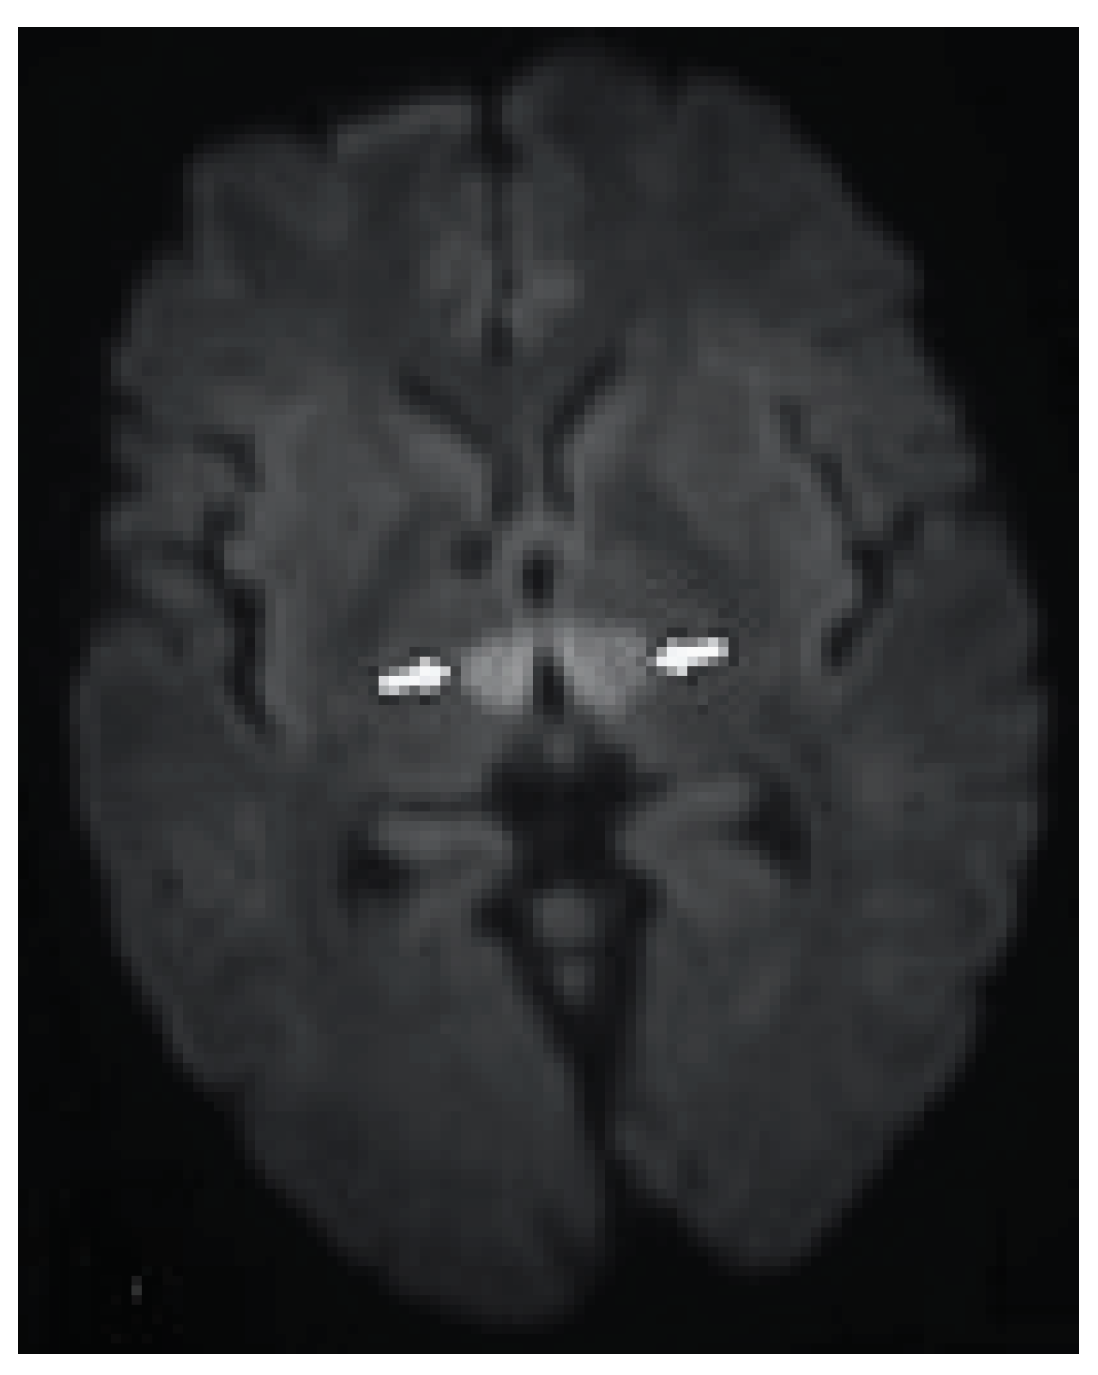

Radiological Investigations: